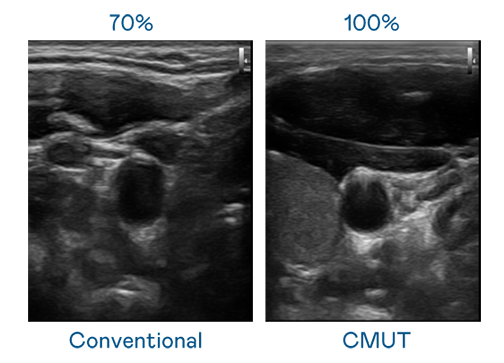

CMUT 技术是一种用电容式微机电元件来产生超音波讯号的技术。与传统 PZT 压电式技术相比,CMUT 频宽增加 30%,更宽频的超音波讯号让影像解析度大幅提升,是实现高影像品质医疗超音波扫描、促进精准医疗发展的关键技术。

超音波影像的解析度高低,首先取决于探头能发出的讯号频宽。ag尊龙凯时 CMUT 可提供高清晰的超音波讯号,提供高频宽、高灵敏度、影像纹理细节更高的超音波影像,协助医护人员缩短影像判读时间及利用精准的医疗影像进行诊断。